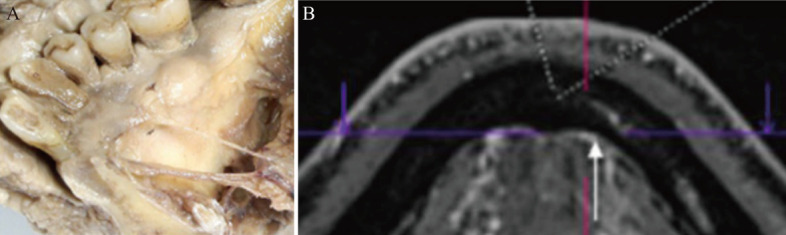

在下颌前区进行种植手术时,可能会损伤下颌切迹管、舌孔、口底血管等重要解剖结构,从而导致口底血肿、窒息、疼痛、麻痹等症状。严重者可危及生命。下颌前牙区牙槽骨空间不足,血管和神经的解剖变异增加了种植手术中血管和神经损伤的风险。一旦发生血管损伤,应进行气道控制和止血;一旦发生神经损伤,应拔除种植体并及早就医。为了避免下颌前牙区种植手术中的血管和神经损伤,必须熟悉解剖结构,术前做好锥形束计算机断层扫描和设计,术中利用数字化技术实现种植体的准确植入。本文总结了下颌前牙区的解剖结构,探讨了下颌前牙区血管、神经损伤的预防策略,并对发生血管、神经损伤后的治疗方法进行了探讨,以期为临床提供参考。

Important anatomical structures such as mandibular incisive canal, tongue foramen, and mouth floor vessels may be damaged during implant surgery in the mandibular anterior region, which may lead to mouth floor hematoma, asphyxia, pain, paresthesia and other symptoms. In severe cases, this can be life-threatening. The insufficient alveolar bone space and the anatomical variation of blood vessels and nerves in the mandibular anterior region increase the risk of blood vessel and nerve injury during implant surgery. In case of vascular injury, airway control and hemostasis should be performed, and in case of nerve injury, implant removal and early medical treatment should be performed. To avoid vascular and nerve injury during implant surgery in the mandibular anterior region, it is necessary to be familiar with the anatomical structure, take cone-beam computed tomography, design properly before surgery, and use digital technology during surgery to achieve accurate implant placement. This article summarizes the anatomical structure of the mandibular anterior region, discusses the prevention strategies of vascular and nerve injuries in this region, and discusses the treatment methods after the occurrence of vascular and nerve injuries, to provide clinical reference.